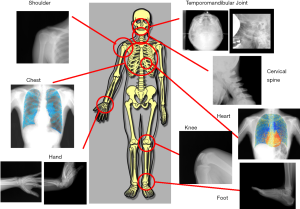

My colleagues and I have developed a screening examination that provides kinetic data through the use of a dynamic X-ray flat-panel detector (FPD) (Figure 1) in our laboratory. This new examination is not based on conventional X-ray fluoroscopy for diagnostic examinations but rather based on functional dynamic radiography (fDR) with the “addition of physiological and functional data that are subjected to computer analysis,” which is similar to systems generally used in initial examinations. Conventional screening examinations (initial examinations) require subjects to “hold their breath” and “keep still,” which results in only a limited amount of diagnostic data being obtained. However, considering major developments in image processing and the digital radiography system, we believe that it is possible to develop an innovative screening system that can provide new diagnostic information. Hereby I provide an overview of the development of this screening system from the initial stages as well as the results of currently ongoing clinical trials. In addition, I provide a summary of reports by other researchers that are related to this research.

Morphological analysis of the function of the joints of extremities

When examining the joints of extremities, it is extremely important to assess motor function. However, nearly all current medical imaging makes use of initial diagnostic imaging based on morphological data using static X-ray images (front, lateral, under stress). Although diagnostic examinations utilize CT and MRI to perform differential diagnoses using 3D anatomical data of soft tissues such as cartilages, tendons, and articular disks, in many cases, subjects are instructed to keep still during the imaging process.

With the introduction of the FPD system, it would not be an exaggeration to say that X-ray imaging has entered the age of the X-ray digital camera and is not unlike a consumer digital camera in convenience and usability. Specifically, recording and performing functional analysis of “movements” of great interest using dynamic imaging as well as recording and assessing 3D “morphologies” that are difficult to visualize (e.g., tomosynthesis) are no longer technically difficult. Below are examples of kinetic examinations and analytical methods performed using dynamic FPD.